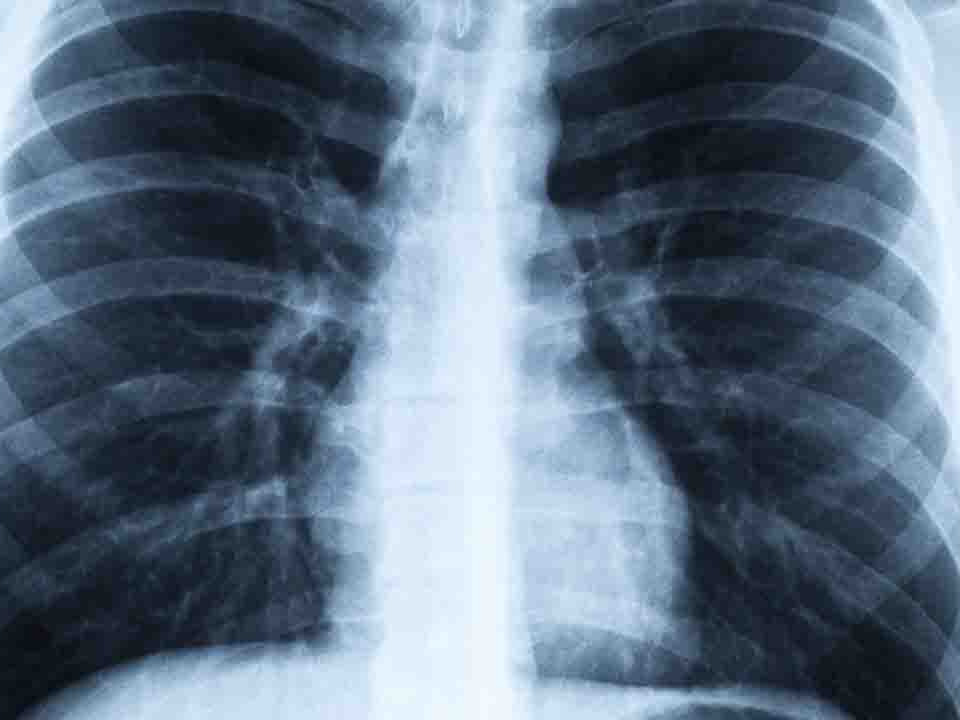

胸部X线检察对老年人肺炎症状的诊断极为重要

胸部X线检察对老年人肺炎症状的诊断极为重要,肺内出现新的浸润灶即可作出诊断,但各种不同的病原体感染的肺部表现却缺乏特征性而不易区分。